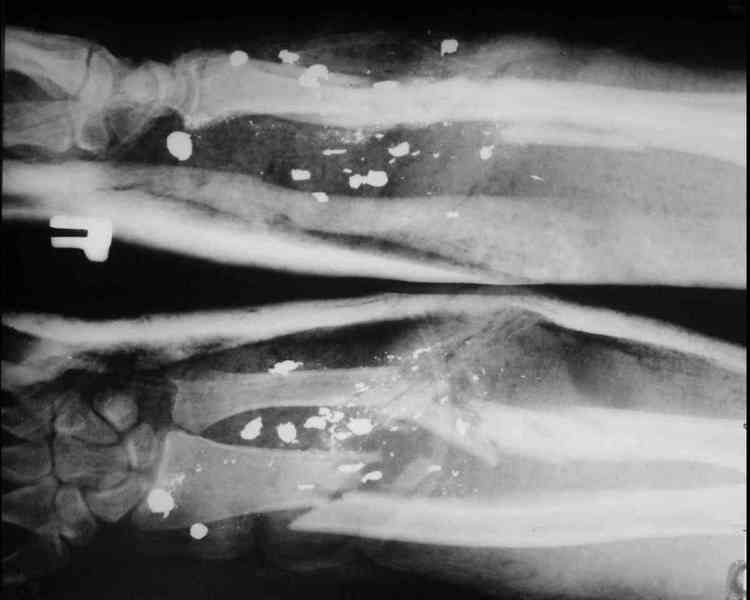

Огнестрельное ранение предплечья

Помогите определиться с тактикой лечения больного с огнестрельным переломом правого предплечья.

Ранение 5.01.08 говорит что взорвался патрон в костре, но это естественно осколочное ранение. В травматологическом отделении одной из больниц проведено ПХО, промывная система,гипсовая повязка от пястно-фаганговых суставов до в/3 плеча, антибиотикотерапия. 17.01 переведен к нам. Состояние ран представлено на снимках. Планируем фиксацию в стержневом апарате, ревизию ран, некрэктомию и готовить раны к пластическому закрытию. У кого какие мнения в плане лечения даного больного.